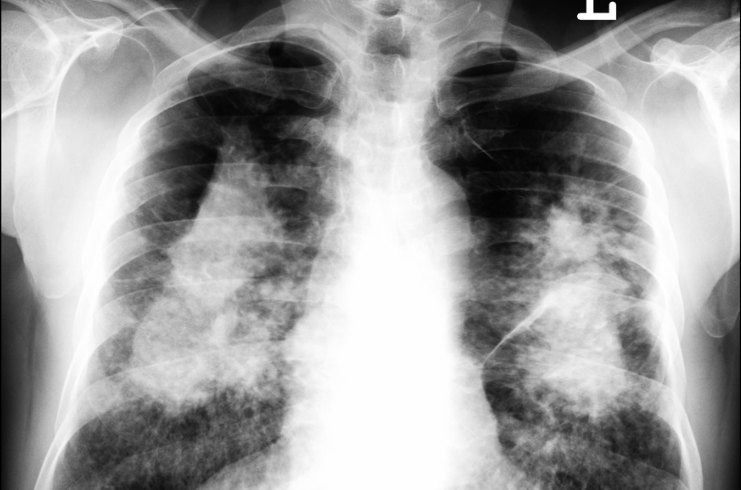

Silicosi

- Descrizione: Malattia respiratoria causata dal deposito di particelle di biossido di silicio, nelle vie respiratorie. È considerata irreversibile e invalidante.

- Senso biologico [!]: Nel tentativo di fagocitare le particelle di silicio, le cellule immunitarie muoiono causando Infiammazione e, successivamente, la fibrosi che impedisce la respirazione. Produce una gran sensazione di incapacità di agire.